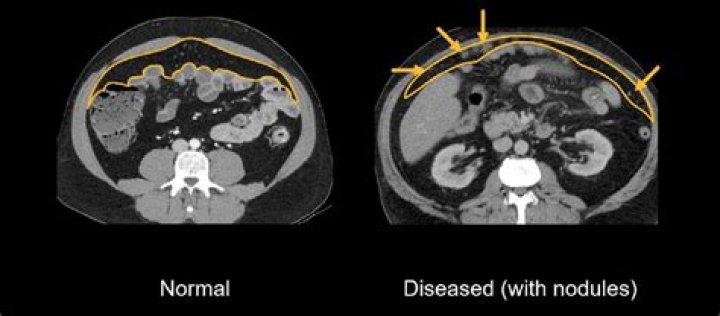

In animals, removing the omentum impacts on the survival of free intraperitoneal malignant cells and there by reduces the rate of local recurrence[72,73]. Because of these observations, the omentum is frequently removed as part of resections for malignancies of various intra abdominal organs[74].

Because removal of the omentum can result in surgical morbidity and longer-term problems with metabolism and peritoneal immunosurveillance, scientists are looking for ways to spare the omentum during treatment for ovarian cancer.